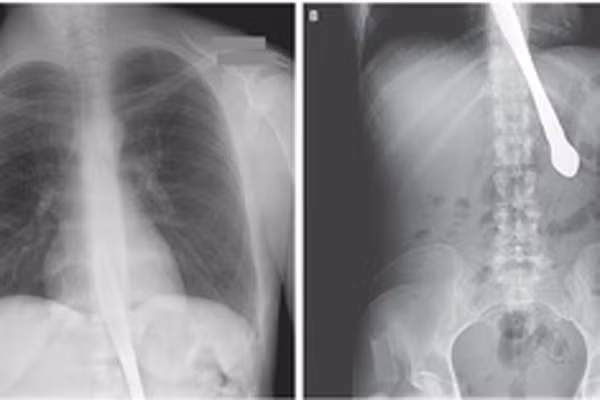

Cậu bé 12 tuổi Chia Jun sống tại Trung Quốc, tranh thủ giờ ra chơi đã chạy ra căng tin của trường mua 1 hộp mỳ ăn liền. Không may, chiếc xe máy điện của 1 phụ huynh trong lớp đi trên sân trường đã lao đến đâm ngã cậu bé làm đôi đũa chọc thẳng vào họng của Chia. các ảnh chụp X-quang cho thấy, đôi đũa tuy xuyên thủng sâu vào cổ họng cậu bé nhưng lại không gây ra nguy hiểm gì đến tính mạng của Chia Jun.

Anh Ou, đến từ Vũ Hán thuộc tỉnh Hồ Bắc của nước này đã tự làm rách toạc một lỗ ở phổi khi đang ngáp. Được đưa vào cấp cứu tại Bệnh viện trung ương Vũ Hán khi cơn đau trở nên mãnh liệt tới mức anh không thể thở nổi. Các bác sĩ phát hiện, anh Ou đã bị tràn khí màng phổi tự phát, hiện tượng xảy ra khi không khí bị mắc kẹt gần một lá phổi.